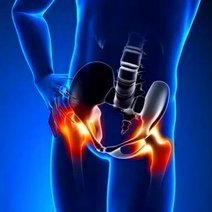

- 强直性脊柱炎,是一种慢性炎性疾病,主要侵犯骶髂关节、脊柱骨突、脊柱旁软组织及外周关节,并可伴发关节外表现。临床主要表现为腰、背、颈、臀、髋部疼痛以及关节肿痛,严重者可发生脊柱畸形和关节强直。西医学名强直性脊柱炎英文名称,所属科室内科免疫内科

- 强直性脊柱炎强直性脊柱炎(AS)是以骶髂关节和脊柱附着点炎症为主要症状的疾病。强直性脊柱炎属风湿病范畴,病因尚不明确,是以脊柱为主要病变部位的慢性病,累及骶髂关节,引起脊柱强直和纤维化

- 强直性脊柱炎强直性脊柱炎是指主要累及双侧骶髂关节、脊柱关节、外周关节和关节周围组织的一种系统炎症性疾病。临床上常见以休息时下腰部(或腰背部)、髋关节或下肢多个大关节疼痛为主要表现。

- 强直性柱炎强直性柱炎强直性柱炎(AS)是一种主侵犯柱,并累及关和周围关的慢性性炎性疾病。类湿性柱炎、类湿中心型等,现称AS。由于本病也可侵犯外周关,并在临床、放射线和病理